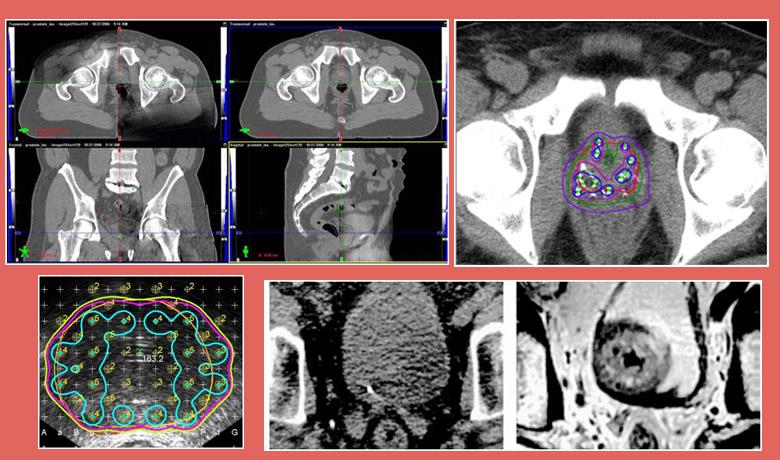

External beam radiation therapy uses high-energy X-rays (photons) to treat prostate cancer. The rays are produced by a linear accelerator, positioned at a distance from the patient’s body. Three Dimensional Conformal Radiotherapy (3D-CRT) is the most frequently used external beam radiation therapy technique, while Intensity Modulated Radiotherapy (IMRT), an improved version of 3D-CRT which focuses the dose on the target and avoids healthy tissues, has been increasingly gaining ground over recent years, especially in terms of treating prostate cancer.

Brachytherapy is a form of radiation therapy in which a radioactive source irradiates the prostate from the inside. This can be achieved using two techniques. Either with permanent seed implantation (radioisotopes) in the prostate gland that cease irradiating 9-12 months after implantation into the patient’s body (LDR – Low Dose Rate Brachytherapy), or with the temporary placement of catheters, which are removed once treatment is completed (HDR – High Dose Rate Brachytherapy).

- IMRT allows radiation oncologists to increase the dose being delivered to the prostate up to 86 Gy, while protecting neighboring healthy tissues. This is the only technique that allows the safe increase of the dose beyond 76 Gy with conventional fractionation or the increase of the dose with subfractionation (larger daily radiation doses).

- Image Guided Radiotherapy (IGRT)

- Fusion of CT planning images with MRI or MRI Spectroscopy images